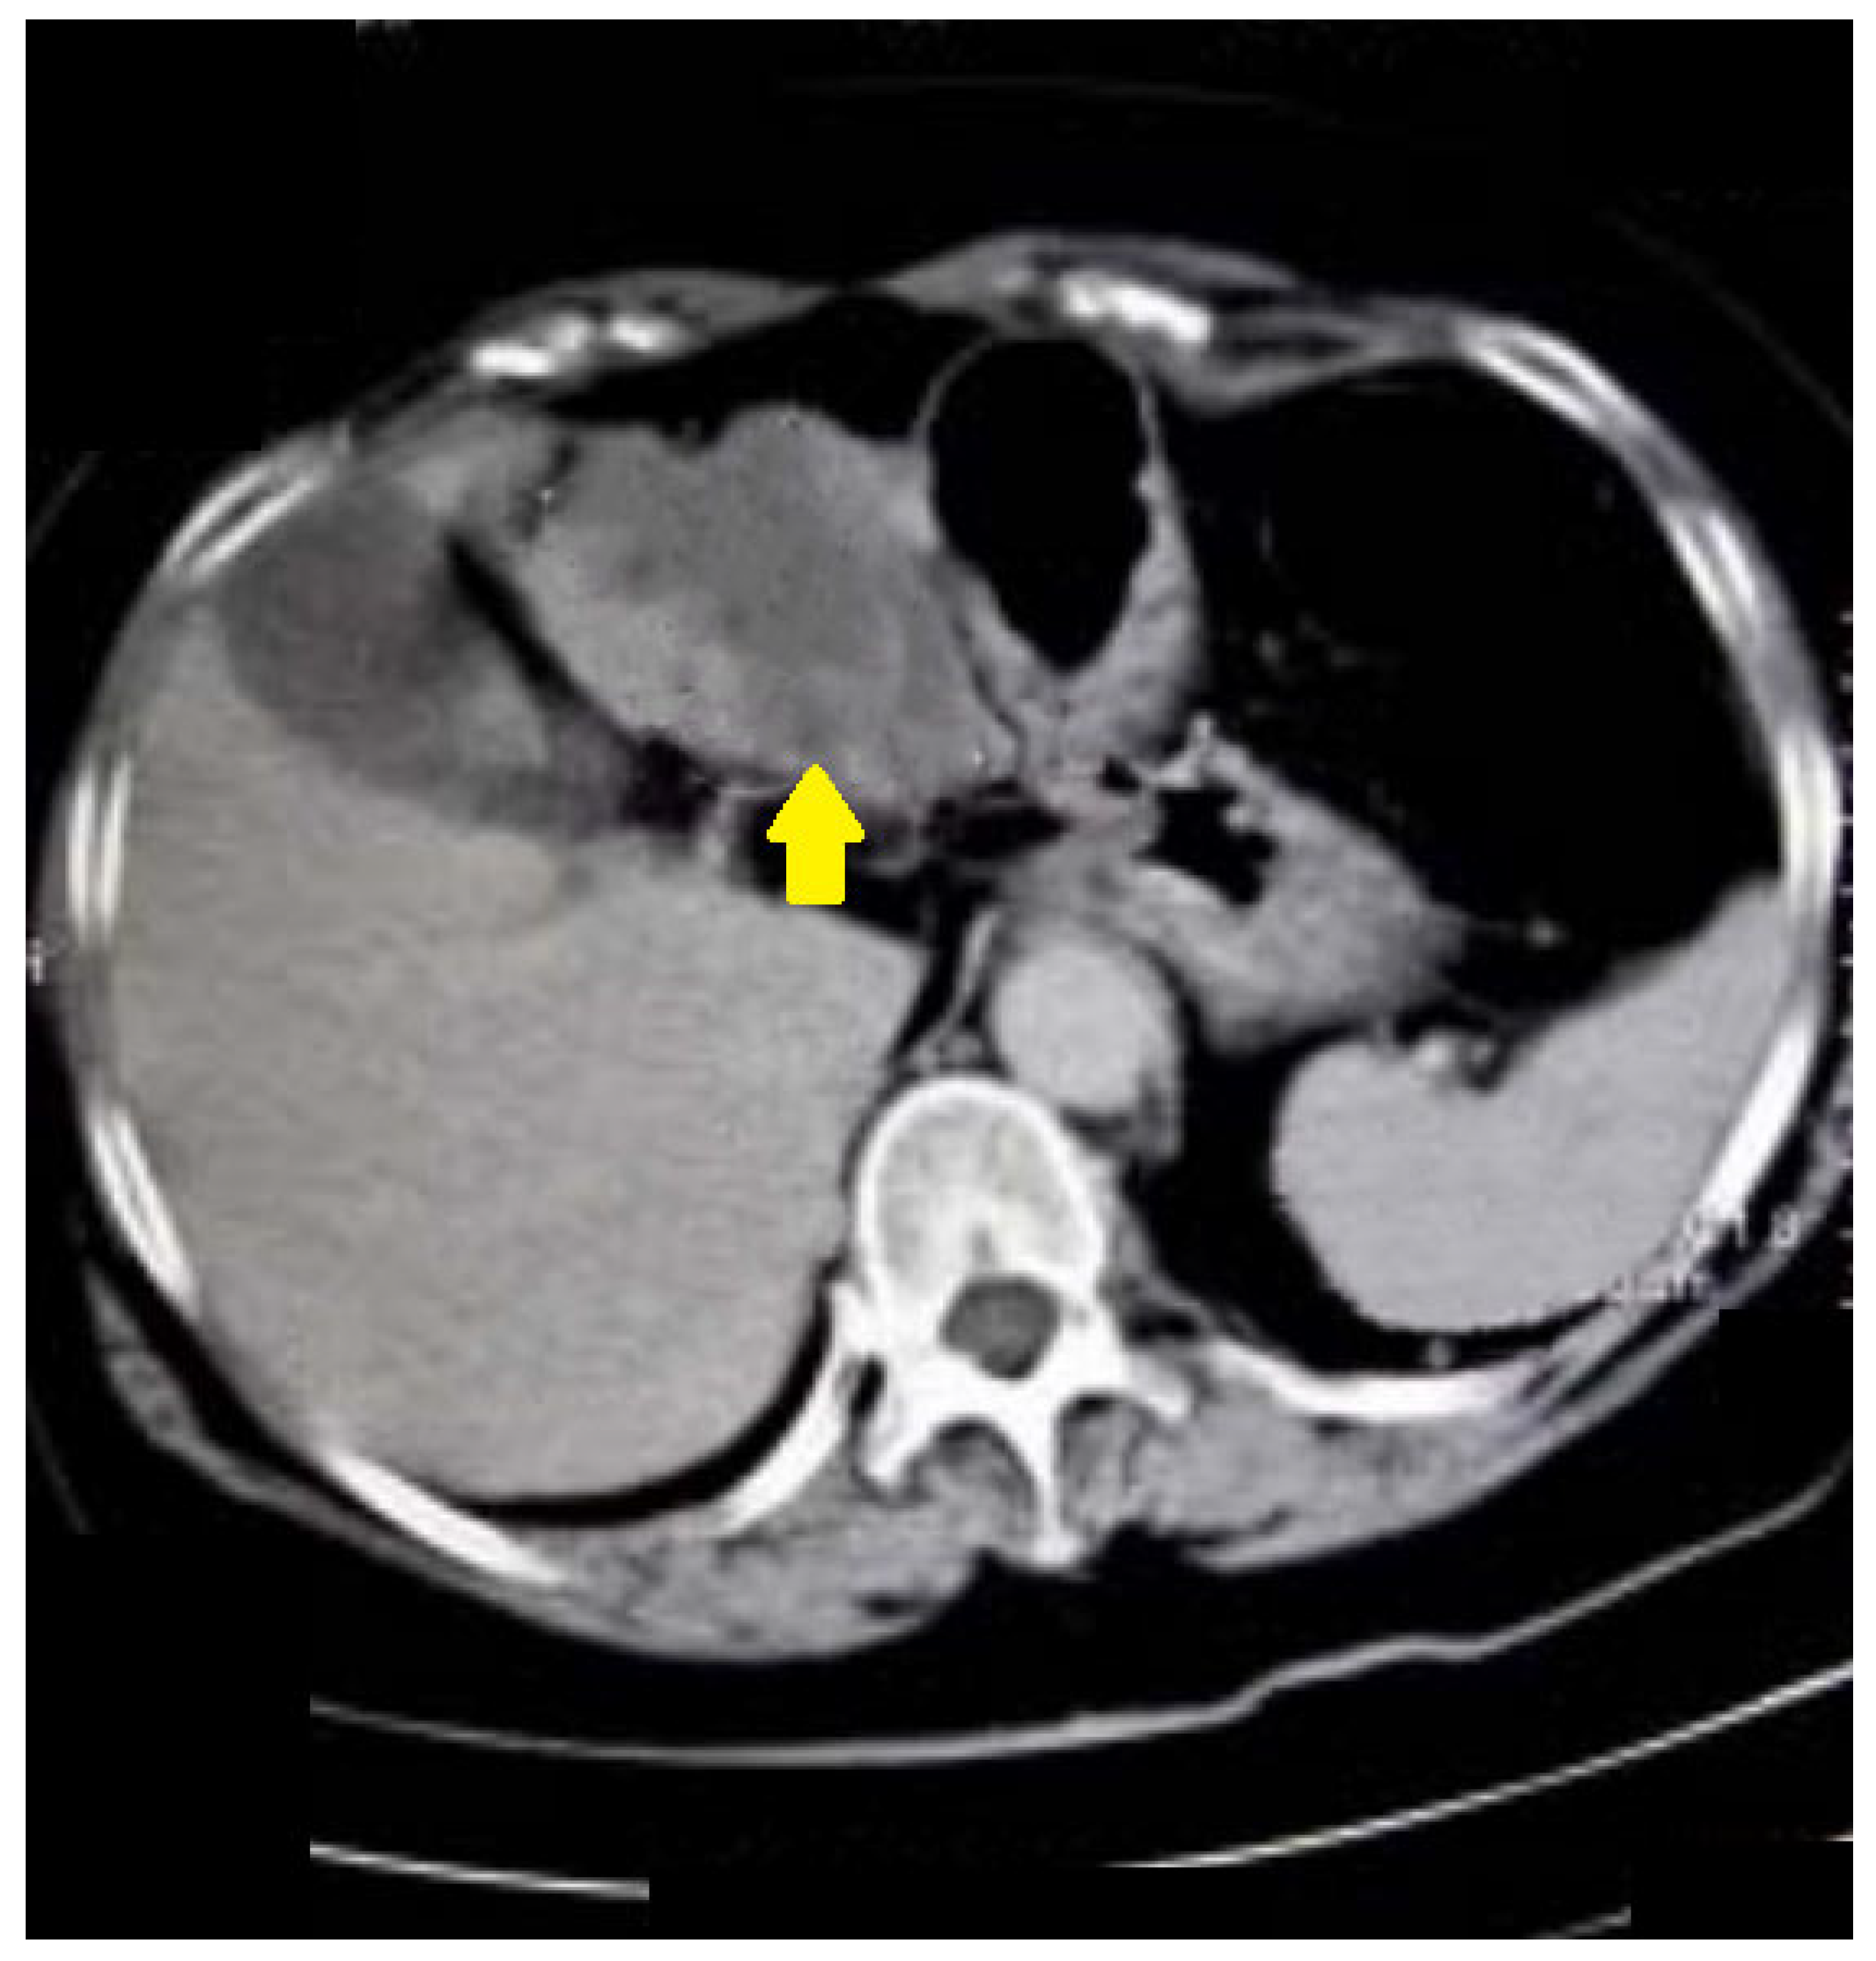

The following case was an 80-year-old patient who underwent FCS, on which there was evidence of compression of the colon. CT colonography showed tumor formation with irregular outlines and inhomogeneous density arising from the caecum (Figure 6).

Figure 6.

CT colonography-axial slice; 80-year-old patient with incomplete FCS obturation from extraluminal origin was suspected (yellow arrow). After CT colonography, cancer of the cecal valve was found.